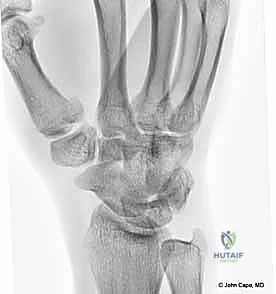

يتكون هذا المفصل من التقاء قاعدة عظم المشط الأول للإبهام (First Metacarpal Bone) مع العظم المربعي (Trapezium) الموجود في صف عظام الرسغ. يُصنف هذا المفصل من الناحية التشريحية على أنه "مفصل سرجي حقيقي" (Saddle Joint). هذا يعني أن الأسطح المفصلية لكلا العظمين تتخذ شكلاً مقعراً في اتجاه ومحدباً في الاتجاه الآخر، مما يسمح لها بالتشابك التام.

2. التصوير بالأشعة السينية (X-rays)

هي الأداة التشخيصية الأولى والأهم. يتم إجراء صور أشعة بزوايا محددة جداً:

* المنظور الأمامي الخلفي (AP View).

* المنظور الجانبي الحقيقي (True Lateral View): وهو ضروري جداً لتقييم مدى الخلع أو الانزياح في المفصل.

* منظور روبرت (Robert's View): وضعية خاصة للأشعة السينية تظهر مفصل الإبهام الرسغي السنعي بوضوح تام وتكشف عن أدق التفاصيل في كسور بينيت ورولاندو.